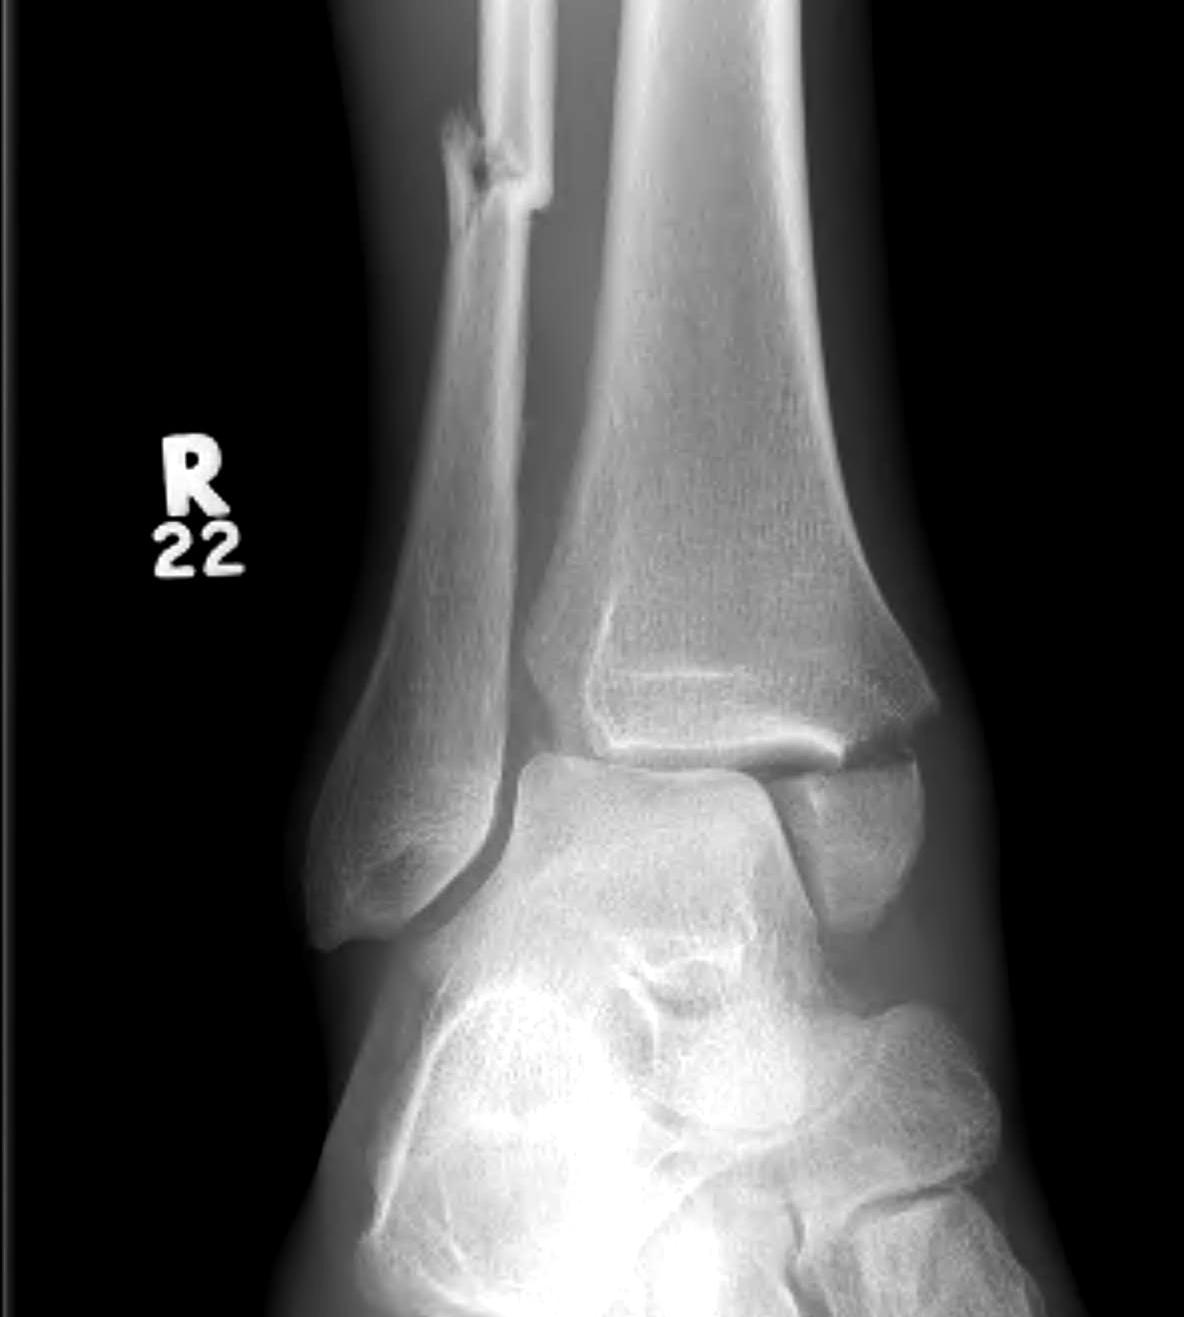

Lateral talar shift / increased medial clear space / deltoid ligament injury

Ankle Fracture Increased Medial Clear SpaceAnkle Fracture Increased Medial Clear Space 2Maisonnerve